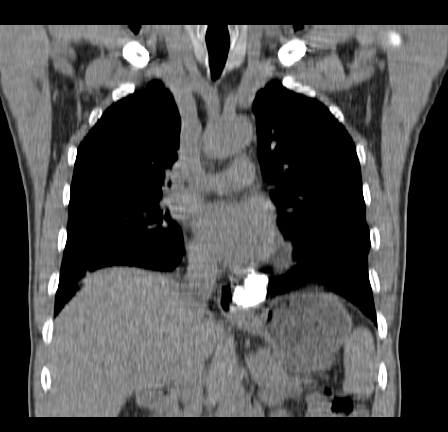

以下是引用影像孺子牛在2009-5-20 23:18:00的发言:[br]左侧后心膈角处类椭圆形钙化灶,最常见的是淋巴结钙化,但太大了不支持,其它如食管囊肿钙化、实性畸胆瘤等。何东西钙化真不好定。

以下是引用zbp537在2009-5-20 20:52:00的发言:[br]钙化灶,来源不好说。